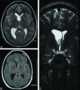

Septum pellucidum neoplasm